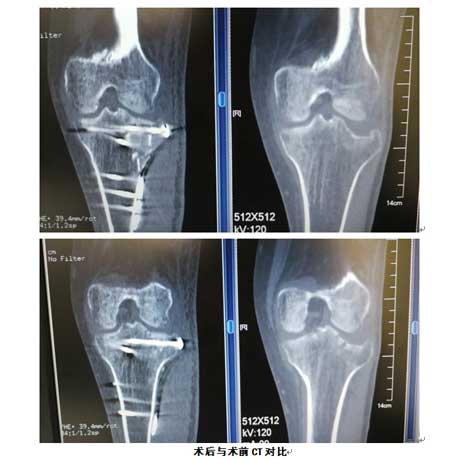

患者张先生,左膝摔伤2月余,入院后诊断为左胫骨外侧平台骨折,SchatzkeII型。X线、CT显示外侧平台劈裂伴塌陷骨折,关节面压缩约1.5cm,关节间隙明显增宽,手术指征明确。因患者骨折为陈旧性,CT可见骨折端已有骨痂生长,骨折块已粘连。传统的手术方法从骨骼表面很难找到明确的骨折线,无法做到精确复位和固定,应用3D打印技术可以解决这一难题。术前行骨折部位薄层扫描CT,将患者股骨影像及数据搜集并记录下来,并通过3D打印技术制作出一个1:1比例的“复制品”,它的直径、长短、骨折形态都与患者真实情况完全相符,甚至患者骨骼上每一块凹陷与凸起,每一点纹理和痕迹都呈现得一清二楚。

术前与患者健侧膝关节C型臂透视对比,可见患侧外侧平台塌陷、外侧关节间隙增宽。

按着术前设计,准确植入钢板螺钉,顺利完成了手术,大大缩短了手术时间,减少了对患者的创伤。术后影像外侧平台高度恢复,钢板螺钉位置准确无误。患者术后膝关节功能良好,顺利康复。